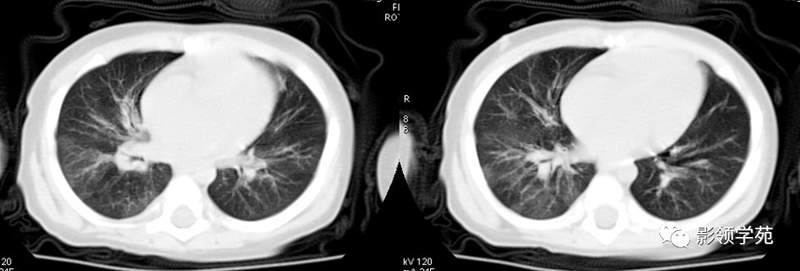

肺结核的渗出性改变:片状、边界模糊

有硬化部分的磨玻璃样变

过敏性肺炎

马赛克征

肺出血(片状、边缘模糊)